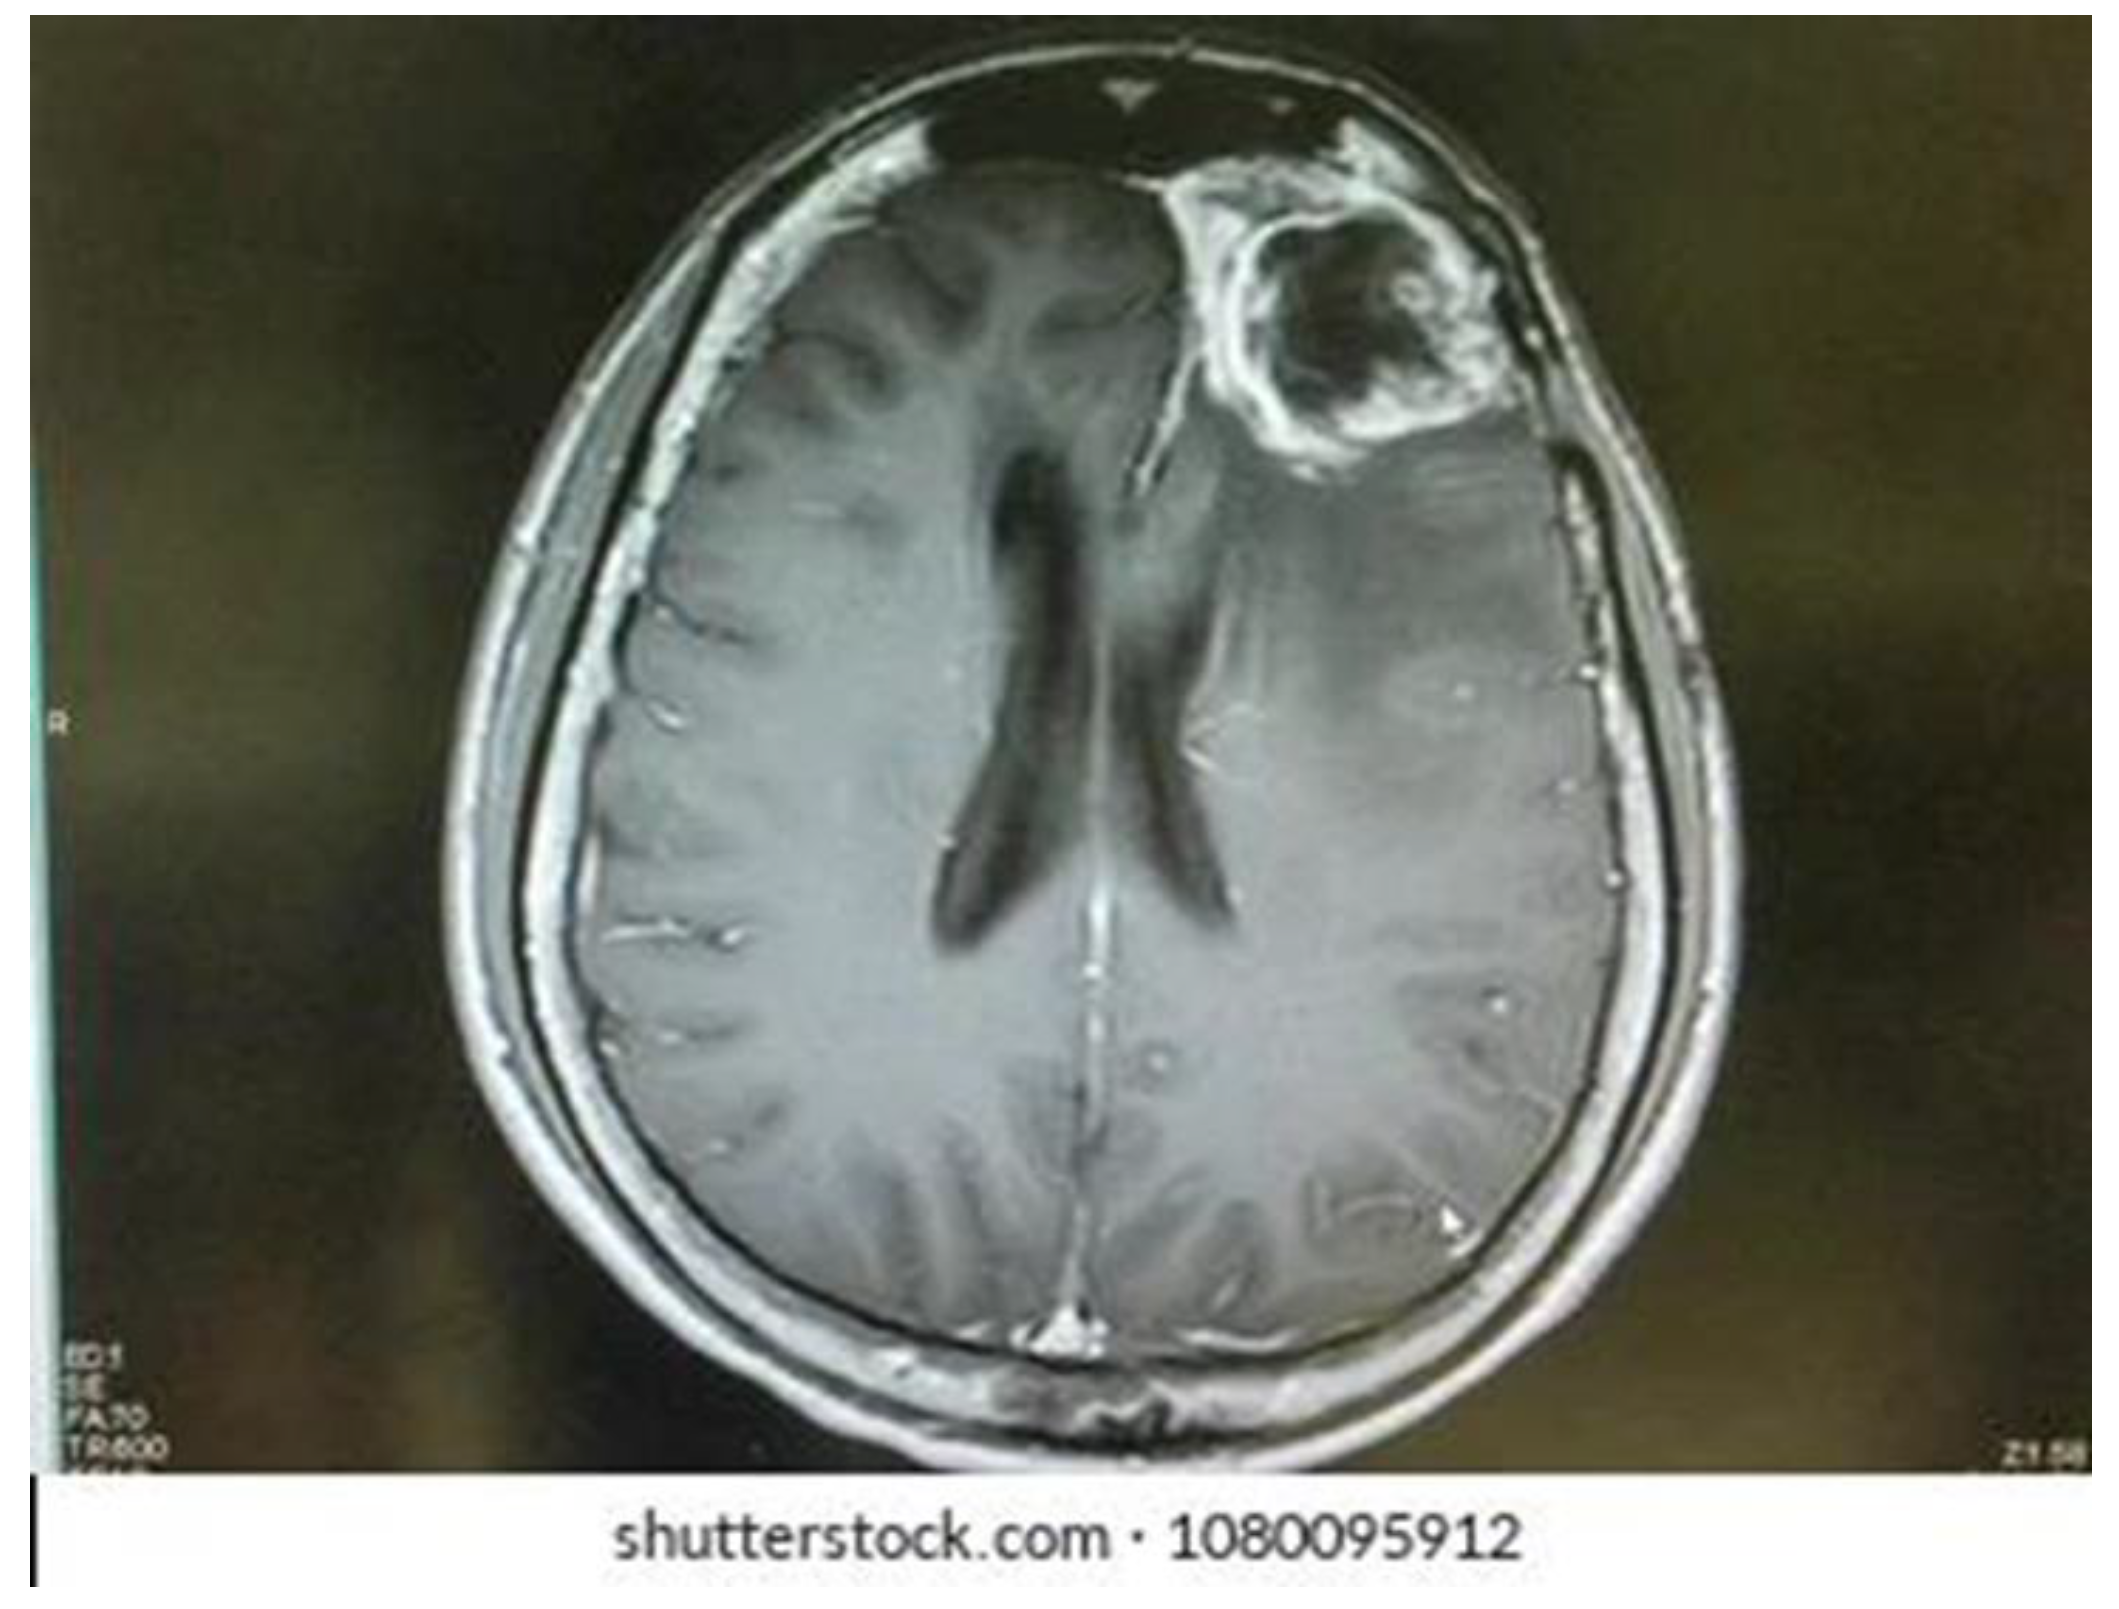

3.1.1. Simulated Microgravity Effects on Glioblastoma Multiforme